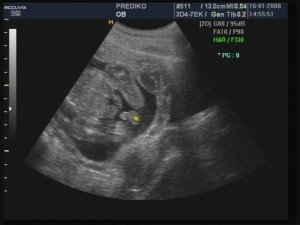

Čekal nás druhý velký UTZ v PREDICU, kam šli maminka s tatínkem spolu. Paní doktorka byla moc hodná, byla nadšená z mého srdíčka, ukazovala našim páteř, ledviny a dokonce viděli moje rtíky a nosík. A potvrdila, že jsem chlapeček! Naši si nechali celé vyšetření natočit na dvd a doma se na něj hned dívali s babičkou a dědečkem. Podle MS 20+4tt a podle UTZ 21+3tt - mám velkou hlavičku

Obrazek